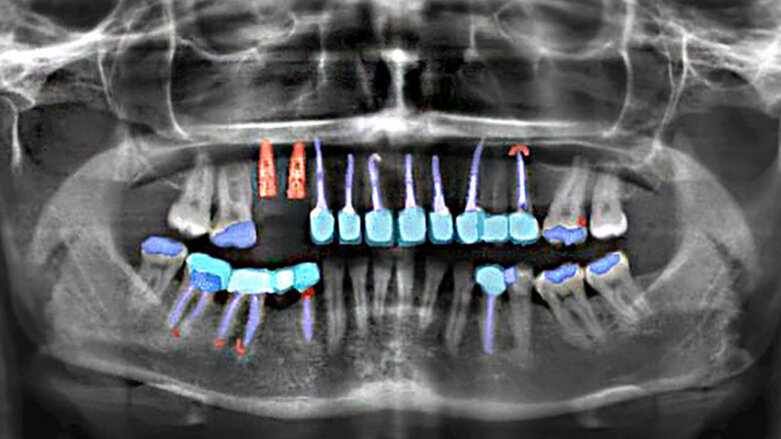

BERLIN, Germany: Dentists at Charité—Universitätsmedizin Berlin, together with data scientists and programmers, have developed dentalXrai Pro—a software program that allows dental practitioners to perform the analysis of radiographs based on artificial intelligence (AI). The new software was designed to help dentists identify pathologies and restorations more accurately and in less time in order to provide optimal treatment and improve communication with patients.

Since most dental practices already take digital radiographs, these can be easily transmitted to dentalXrai Pro. In order to deliver a pre-analysed image within a very short time, the browser-based software accesses high-performance computers and a whole range of algorithms.

These algorithms are the result of in-depth software training using a very large data set of dental radiographs, including panoramic and bitewing images. Dentists from around the world identified tens of thousands of pathological changes and traces of previous dental treatments on the radiographs. This data was then fed to the artificial neural networks, enabling them to distinguish between different findings, such as caries, infections and root canal fillings.